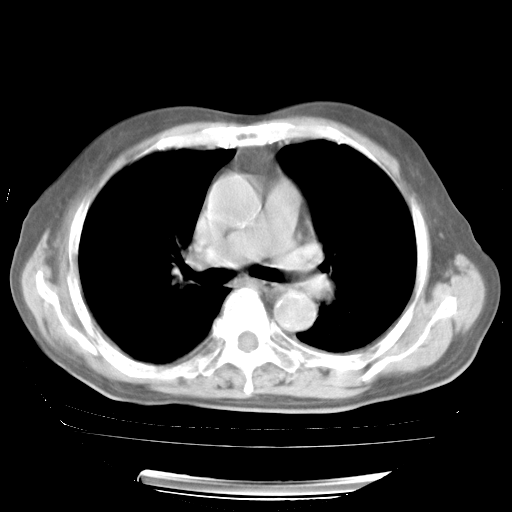

4月28日肺部CT——再次出现类似去年5月9日——透光度降低,“间质性”改变。

4月28日肺部CT——再次出现类似去年5月9日——磨玻璃样、间有“粟粒样”改变。

4月28日肺部CT

个人阅读4.14日肺部CT平扫:纵隔窗无异常,但肺窗示:双下肺内、后基底段有片絮状侵润影,部位以后基底段为著,以间质改变为主,呈急性肺泡炎征像,和首次住院影像学有相似之处。仅是个人读片,明日请相关专家再读片哈。其它建议同上。